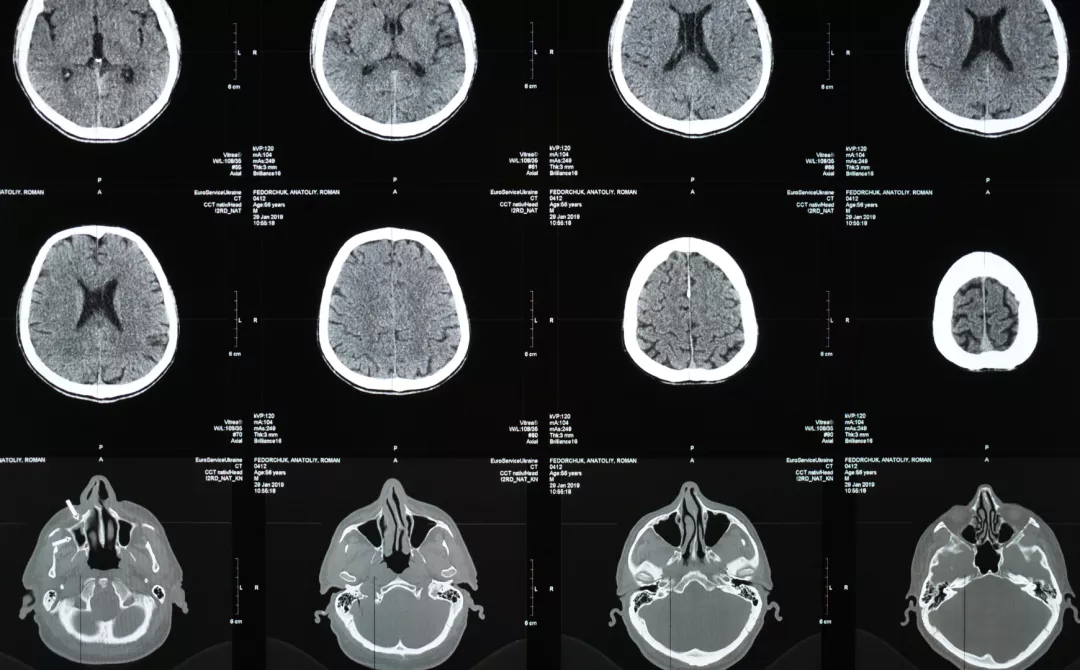

Voorbeelden van subklinische parameters voor ziekteactiviteit zijn nieuwe laesies op MRI (Magnetic Resonance Imaging) of hersenatrofie2.

Illustration of brain MRI scans

Artikel

3 mins

Multiple sclerose (MS): Diagnose